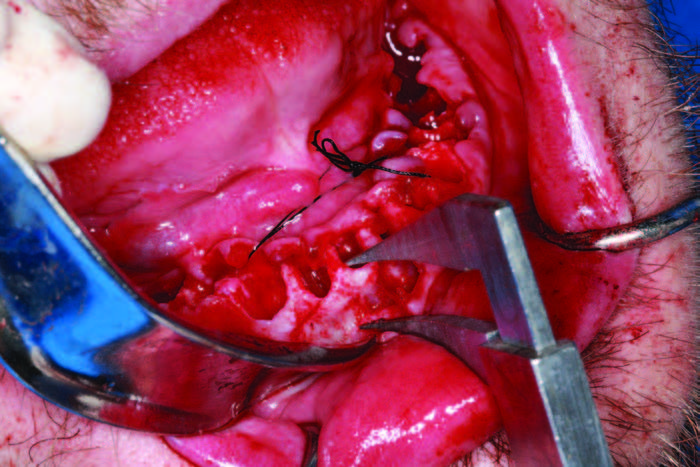

After assessing the patient’s vitals and performing sterile protocol to include a Salvin Split Drape (Salvin Dental Specialties), a facial scrub, and oral chlorhexidine rinses, the patient was anesthetized and extractions were done (Physics Forceps [Golden- Dent]). Piezosurgery (mectron) was also used to sever periodontal ligaments, clean sockets, and level and smooth bone. Physics Forceps are unique surgical forceps that use the alveolar bone as a fulcrum so the tooth can be atraumatically rotated out of the socket. The beaks of the forceps engage the lingual or buccal cervical area and, with a gentle rotating motion, the tooth is released from the periodontal ligament and then removed with traditional forceps (Figures 4a and 4b).